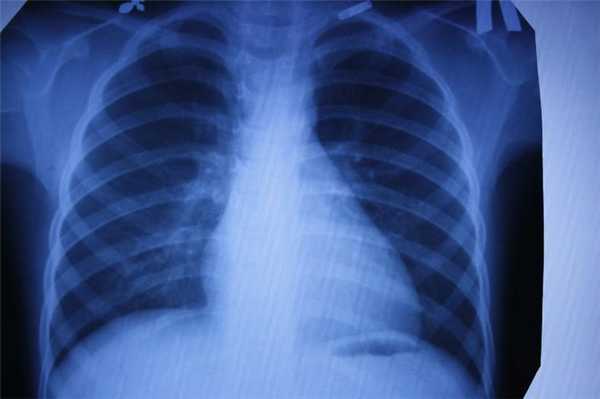

- воспаление легких;

С помощью компьютерной томографии в медицинских центрах СПб проводят скрининг рака легких у курильщиков. Такая томография позволяет выявить в 2 раза больше опухолей на ранней стадии. Простая флюорография (на базе рентгена) рак легких не показывает, поскольку плоскостное изображение не видит маленькие очаги опухоли, а вот на КТ можно визуализировать новообразование до 1 мм величиной.

Принцип работы рентгеновского аппарата заключается в том, что рентгеновские лучи, проходя через разноплотную среду исследуемой области, по-разному ослабляются: более плотная костная ткань в значительной степени поглощает рентгеновское излучение, менее плотная подкожно-жировая клетчатка ослабляет его в небольшой степени, а воздух, содержащийся в околоносовых пазухах или легких, не задерживает совсем. Эти неравномерно ослабленные пучки рентгеновских лучей, попадая на светочувствительный слой пленки, формируют рентгенограмму — изображение, которое отображает все структуры исследуемой области, наслаивая их друг на друга. При этом получаемый снимок позволяет определить форму, размеры и строение исследуемой области, выявить или заподозрить структурные нарушения, а исследование в двух или нескольких проекциях позволяет определить локализацию выявленных изменений. Чаще всего рентгенография используется для исследования костей, легких, почек, кишечника.

Несмотря на более безопасную и эффективную работу современных аппаратов, часто проходить компьютерную томографию все же не рекомендуется из-за возможного воздействия на организм рентгеновского излучения. Тем не менее, компьютерная томография является ведущим методом диагностики заболеваний органов грудной клетки и легких, надпочечников и костно-суставной системы.

Каждый метод дает разную информацию об исследуемых органах. Если говорить в целом, то КТ идеально «видит» легкие, и превосходит все другие методы в выявлении патологии дыхательной системы: и МРТ и рентген и флюорографию.

Для выявления патологии легких также назначают рентген и флюорографию…

Если речь идет о профилактическом осмотре, ежегодной диспансеризации, и у человека нет никаких жалоб - классическое рентгеновское исследование, которое дает меньшую, чем КТ лучевую нагрузку, можно считать достаточным. Но если пациент находится в группе риска по развитию рака легких (например, это курильщик с серьёзным стажем), лучше сразу сделать более информативную КТ. Андрей Дмитриевич Каприн, главный онколог России, рассказывает, что благодаря огромному количеству КТ- исследований легких, которые были сделаны за время пандемии, удавалось выявлять рак легких на самых ранних стадиях и множество других, не связанных с COVID-19 патологий. Низкодозовая КТ - лучший метод скрининга рака легких, она позволяет увидеть зарождающийся опухолевый процесс размером 2-3 мм и самые минимальные изменения, которые рентген может и пропустить.